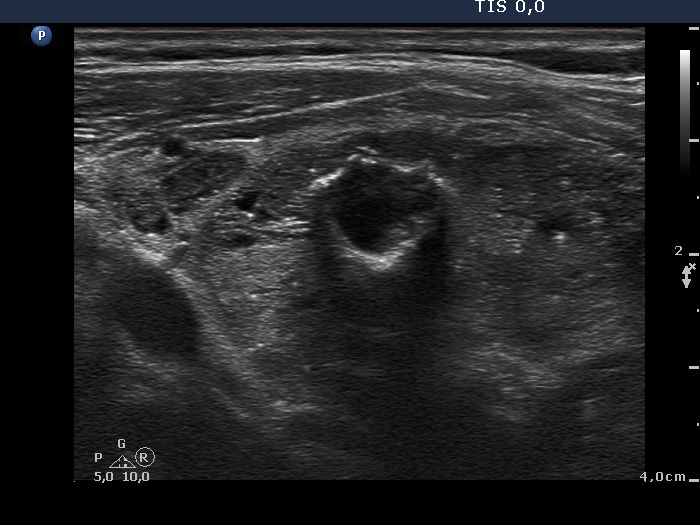

Lower part of the right lobe

|

This nodule has multiple coarse calcifications and proliferation of a connective tissue (arrowheads and arrows).